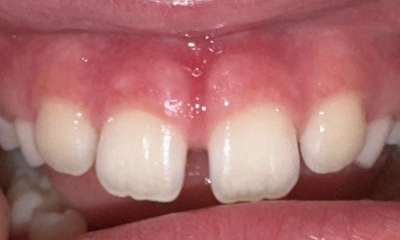

CO2 Laser using to perform a frenectomy or lip release. The use of CO2 laser allows for treatment to completed very quickly with minimal tissue bleeding. Gingival tissues heal beautifully after laser treatment.